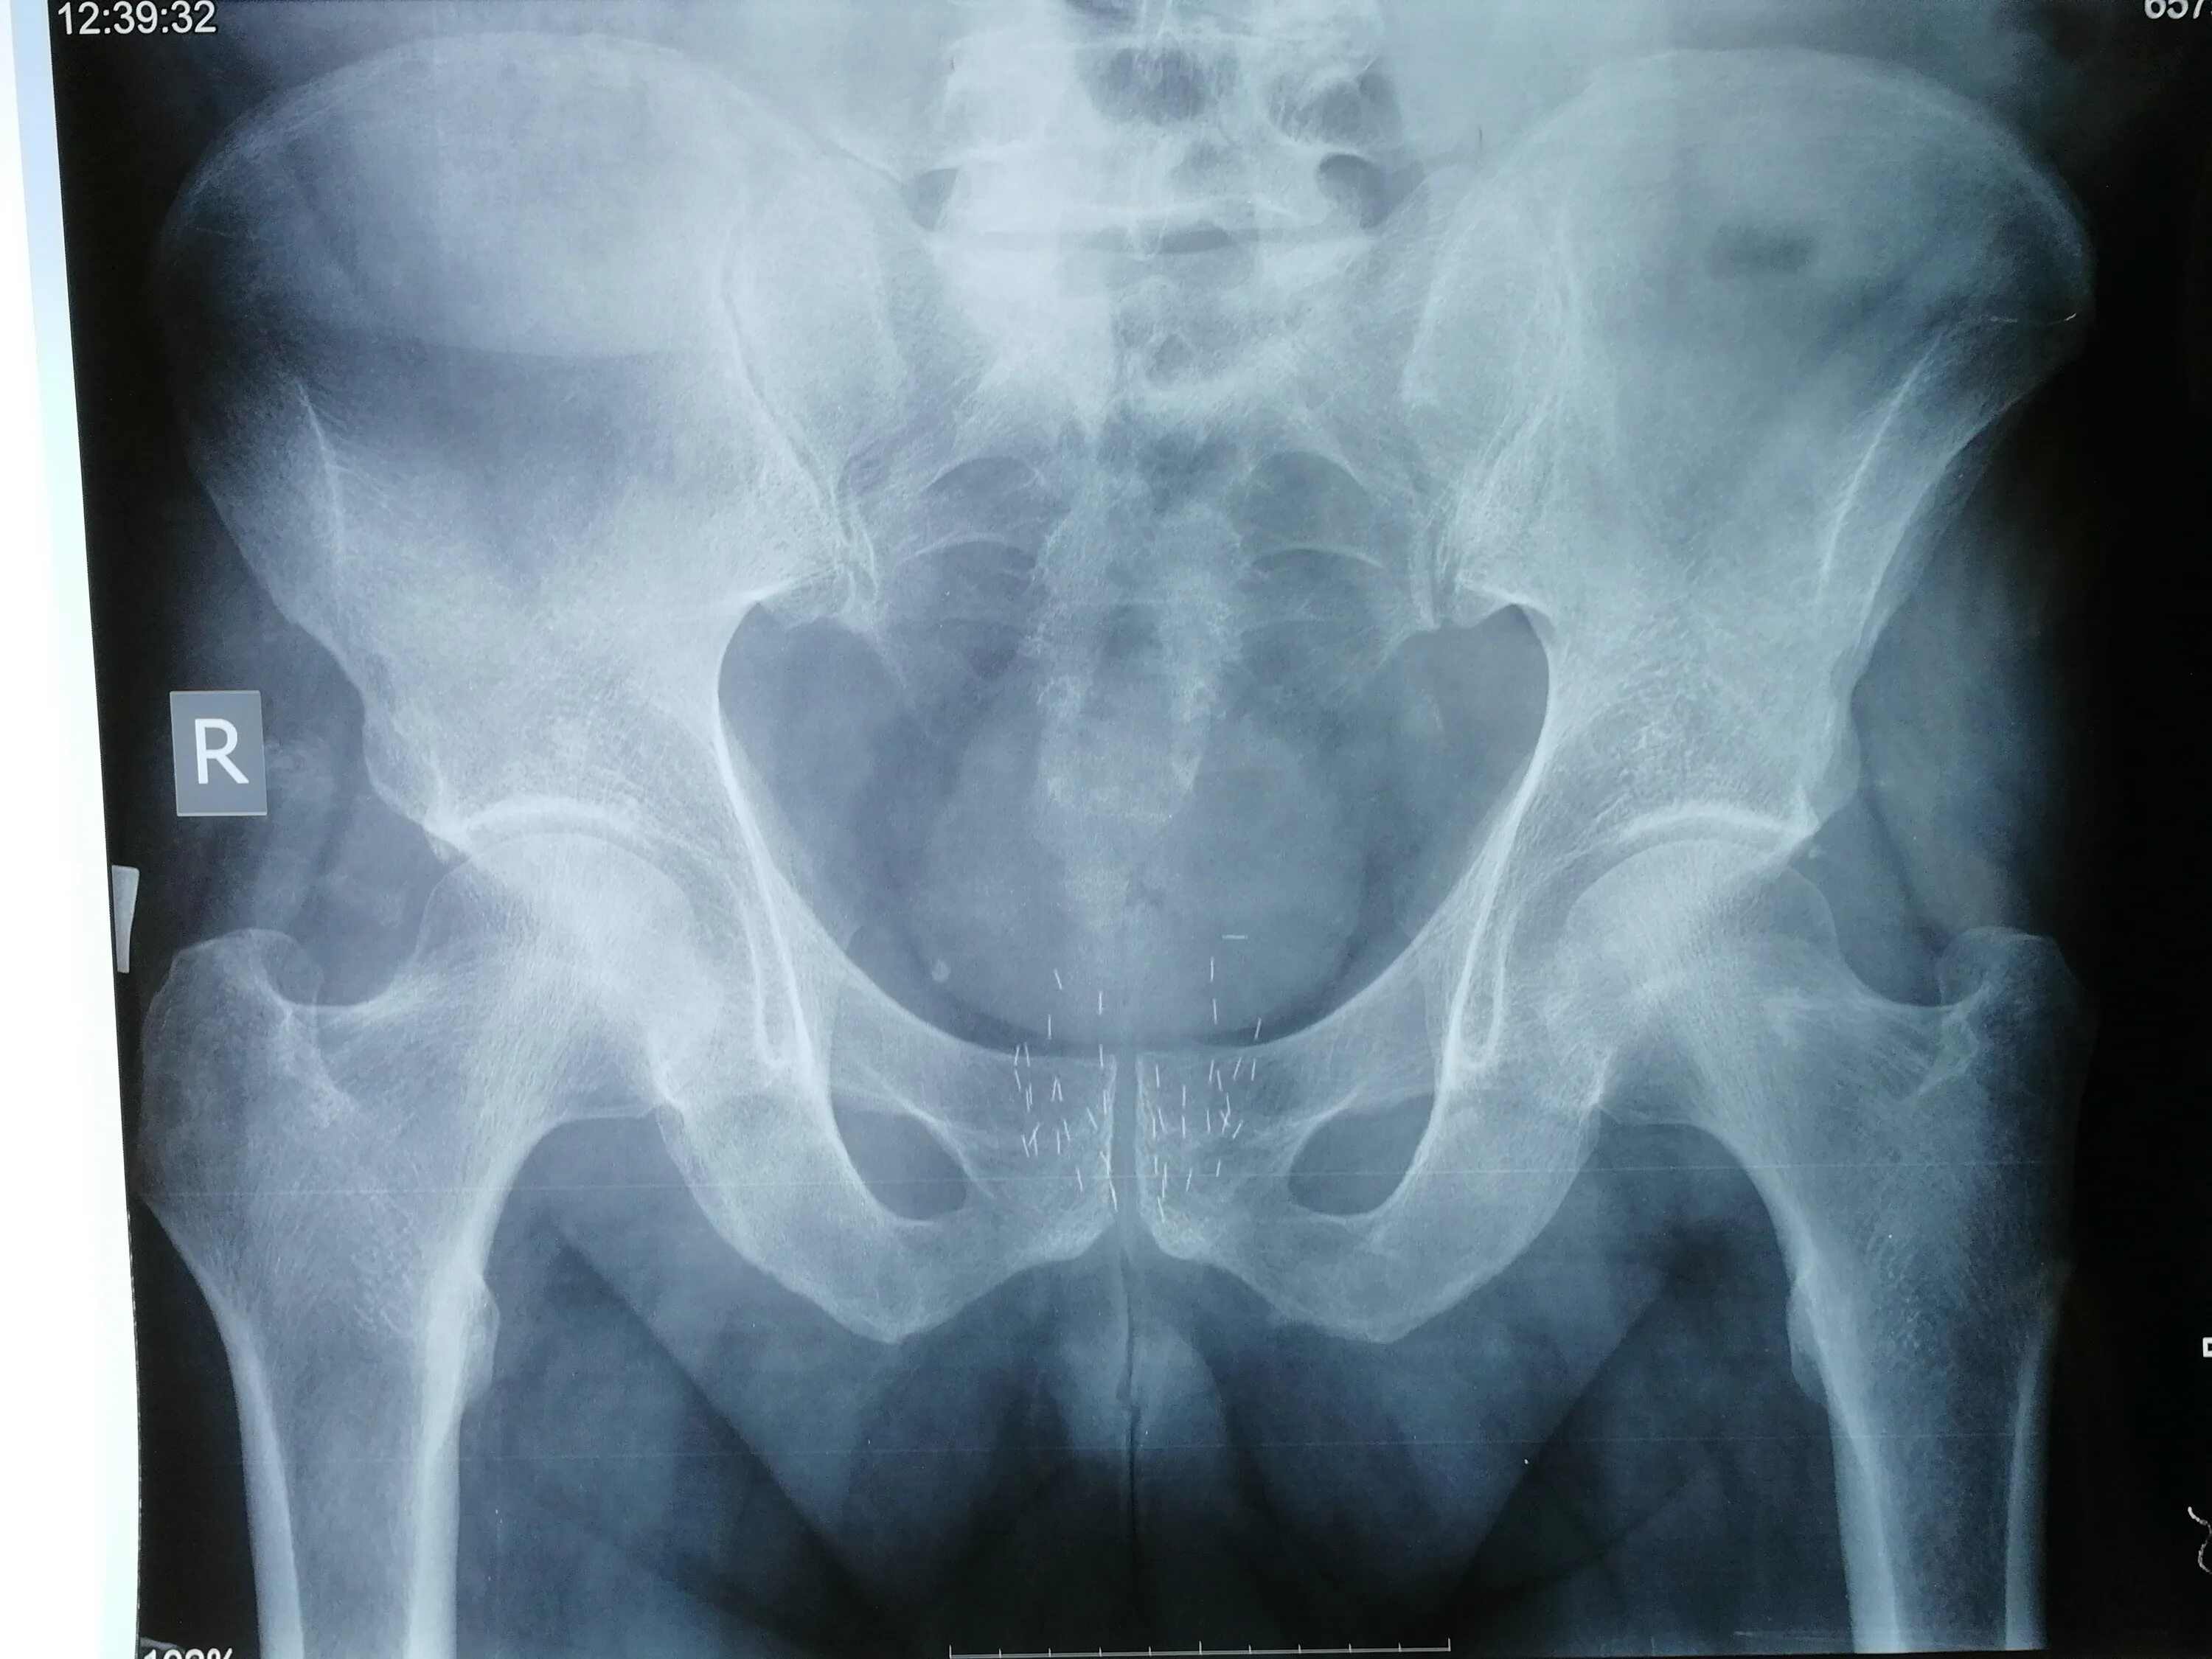

Метастазы в тазобедренном